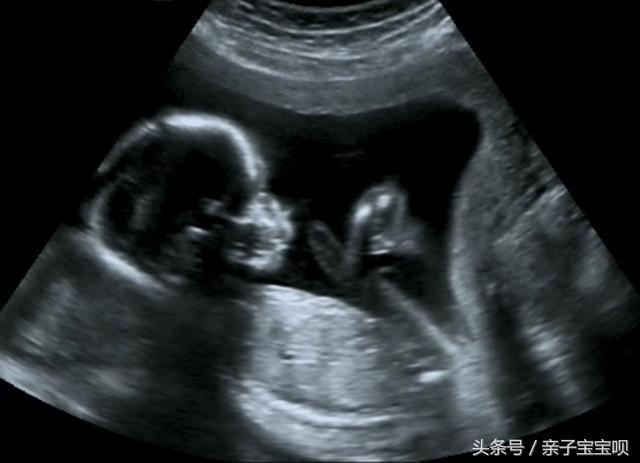

哪知道婆婆拦着不让去,因为是个女孩,婆婆怎么都不愿意生下来,于是就在医院的走廊里面母子二人争吵起来。随着娜娜呼吸声越来越弱,周围的医生也是十分的着急,这时候医生检查发现胎儿的一只手都伸出来了,似乎在抢救,吓得医生赶紧让老公拉开婆婆,准备手术。